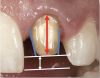

The most important factors to consider in preparing teeth for single-unit restorations are the taper (convergence), height (clinical crown height-how much tooth structure is above the gingiva and the height of the preparation), and reduction (Figure 1).6 Less than or equal to 20 degrees of taper or convergence is clinically appropriate. Overly tapered preparations will prevent the final restoration from being retentive. A preparation that is modestly parallel, while still achieving a good draw, is optimal. A 4-mm crown height is minimally adequate. If the height of the preparation is less than 4 mm, additional retentive features should be considered, such as slots and grooves in the preparation.

Fig 1. The most important factors to consider in preparing teeth for single-unit restorations are the taper, height, and reduction.

Figure 1